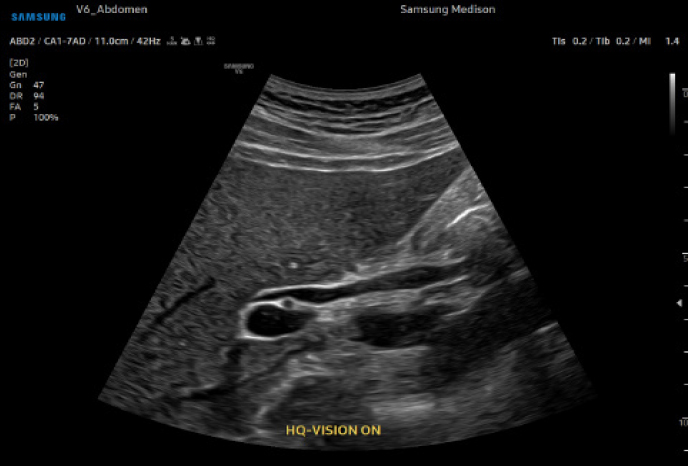

비침습적 프리미엄 초음파 장비를 통해 선명하고 정확한 검사가 가능합니다.

Samsung V6 Ultrasonic

이미지 해상도 극대화, 노이즈 최소화로 장기의 경계부를 선명하게 관찰

저강도 초음파 기술로 신체 조직 위험 최소화

복부간담도계, 비장, 소화기계, 비뇨기계, 부신, 생식기계, 복강 림프절